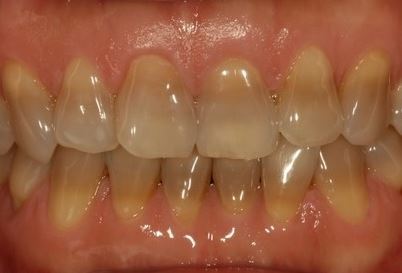

- 나이: 나이가 들면서 치아의 법랑질이 얇아지고, 그 아래에 있는 상아질이 드러나면서 치아가 점점 노래집니다.

- 치아 미백: 내부 착색도 미백 치료를 통해 어느 정도 개선할 수 있지만, 외부 착색보다는 어려울 수 있습니다.

- 라미네이트: 치아 표면에 얇은 세라믹을 부착하는 라미네이트는 내부 착색을 완전히 덮어버리는 방법입니다.

- 크라운: 심한 착색이 있는 경우 크라운(치관)을 씌워 변색된 부분을 완전히 감출 수 있습니다.